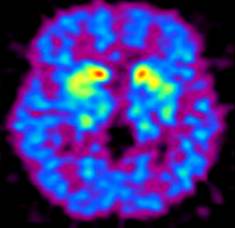

图3,晚期PD患者,碳11-CFT显像,双侧壳核摄取减低